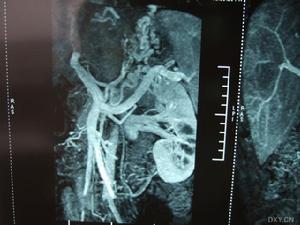

布加氏綜合症(inferiorvenacavasyndrome簡稱IVCS)是由於下腔靜脈受鄰近病變侵犯、壓迫或腔內血栓形成等原因引起的下腔靜脈部分或完全性阻塞,下腔靜脈血液回流因之障礙而出現的一系列臨床征侯群。布加綜合症的治療分為兩種:

介入治療適應證Eqachi(1974)首先報導套用球囊擴張技術治療下腔靜脈膜性閉塞獲得成功,為治療布加征開闢了一條新的途徑;國內相繼也開展了此項手術,該方法以其較好的有效率、微小的創傷、安全、經濟、快捷、併發症少等優點,特別是近年研製的超聲導管和切割導管、生物可降解支架和帶肝素膜支架的臨床套用,使介入治療成為布加綜合徵Ⅰ、Ⅱ型的首選術式和主要方法。

如肝腫大、頑固性腹水、上消化道出血、脾大、脾亢、胸腹壁靜脈曲張、下肢水腫及色素沉著等。《布-加綜合症的介入治療》一書由徐州醫學院製作,人民衛生出版社出版,國家衛生部CAI課件,該課件詳細介紹了布-加綜合徵(Budd-Chiarisyndrome)的臨床表現以及影像診斷,通過臨床案例詳細解說,適合醫學院師生以及臨床醫師學習使用。

本CD-ROM為衛生部醫學CAI課件。本課件使用大量珍貴的臨床病例圖片、錄像、動畫和文字,配以解說,詳細介紹了布-加綜合徵(Budd-Chiarisyndrome)的臨床表現以及影像診斷,重點介紹其治療方法,主要包括適應證和禁忌證、介入治療器械、介入治療方法、最新進展、介入術後處理、併發症及處理。課件中附有練習題。課件內容豐富,資料寶貴,是學習布-加綜合徵的不可多得的輔助教材。本CAI課件由徐州醫學院製作,適用於醫學院師生以及臨床醫師學習使用。